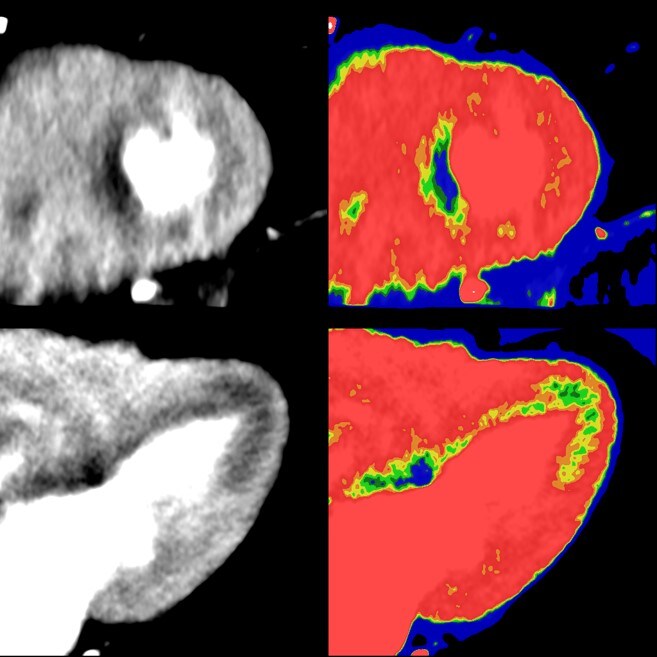

Ehime University School of Medicine “Due to detection of myocardial ischemic area in preoperative evaluation, Perfusion CT with IMR is able to detect it. We think that it might be possible to diagnosis with high accuracy, because Cardiac CT is able to assess morphology and function simultaneously. IMR can be used to conduct dynamic perfusion study with low radiation dose. It is possible to enhance contrast between ischemic and normal myocardium by using low-kV technique with IMR.”

Japan

Dr. Mochizuki, Teruhito Kido & Hikaru Nishiyama